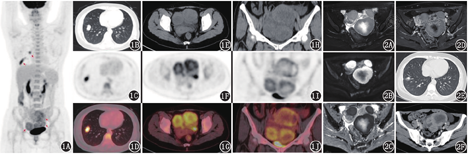

患者女,33岁,早孕超声检查发现双侧卵巢占位,拟择期入院手术治疗。半个月后于本院行人工流产,1个月后出现左上腹持续痉挛性疼痛,伴恶心呕吐,后以腹痛原因待查入院。盆腔MRI提示:双侧附件区多发占位。肿瘤标志物:糖类抗原125 (carbohydrate antigen 125, CA125): 76.9(括号中为正常参考值范围,下同;0~35) kU/L,神经元特异性烯醇化酶(neuron specific enolization, NSE): 51.88(0~18) μg/L,人附睾蛋白4: 171.8(0~140) pmol/L。否认家族成员有类似病史。为进一步明确卵巢病变性质,行18F-FDG(北京原子高科股份有限公司提供)PET/CT(德国Siemens Biograph mCT-64)显像(图1),提示右肺下叶恶性病变,盆腔肿物考虑恶性,倾向原发卵巢癌,不除外肺恶性肿瘤转移。

患者在超声引导下行卵巢肿物穿刺术,病理结果提示:具有神经内分泌分化的小细胞恶性肿瘤,不除外原发性卵巢小细胞癌-肺型(small cell carcinoma of the overy-pulmonary type, SCCOPT),也不能除外小细胞肺癌(small cell lung cancer, SCLC)转移至卵巢。免疫组织化学(简称免疫组化)检查结果:雌激素受体(-),孕激素受体(-),威尔姆瘤核蛋白-1(-),P53(-),细胞增殖核抗原Ki-67指数(约70%+),突触素(synapsin, Syn;+),嗜铬素A(chromogranin A, CgA;+),甲状腺转录因子-1(thyroid transcription factor-l, TTF-1;+)。后患者行阿替利珠单克隆抗体1.2 g D1+依托泊苷150 mg D1~D3+顺铂30 mg D1,40 mg D2~D3治疗,复查肺和盆腔CT示病变均变小(图2)。综合病理和PET/CT检查,最终诊断为SCLC卵巢转移。